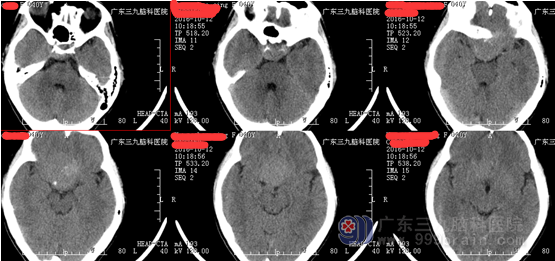

王女士,40岁, 5年前开始出现右眼视物模糊,1年前开始出现左眼视物模糊,为求治疗,来我院就诊。病人由神经外一科接诊,完善相关术前检查,结果示:肿瘤组织包绕神经、动脉,考虑到手术的风险性,科室组织专家反复进行术前讨论,拿出最佳的手术方案,由神经外一科主任张良主刀完成。

行全麻下右侧扩大翼点入路鞍结节脑膜瘤切除术。术中见右侧视神经、颈内动脉被肿瘤包绕,肿瘤血供丰富,肿瘤起源于鞍结节及鞍隔。术中全切肿瘤,神经、血管、垂体柄完好。术后病理示:鞍区脑膜瘤,部分为过渡细胞型,部分为血管瘤型脑膜瘤,WHO I级。术后左侧视力同术前,右侧视力较术前稍差。 经系统的治疗后康复出院。